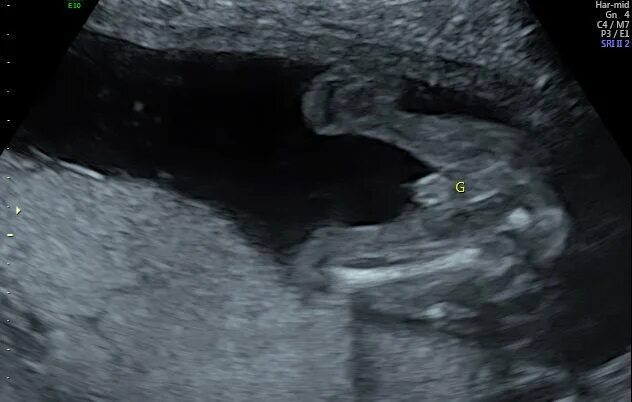

Узи 17 недель девочка